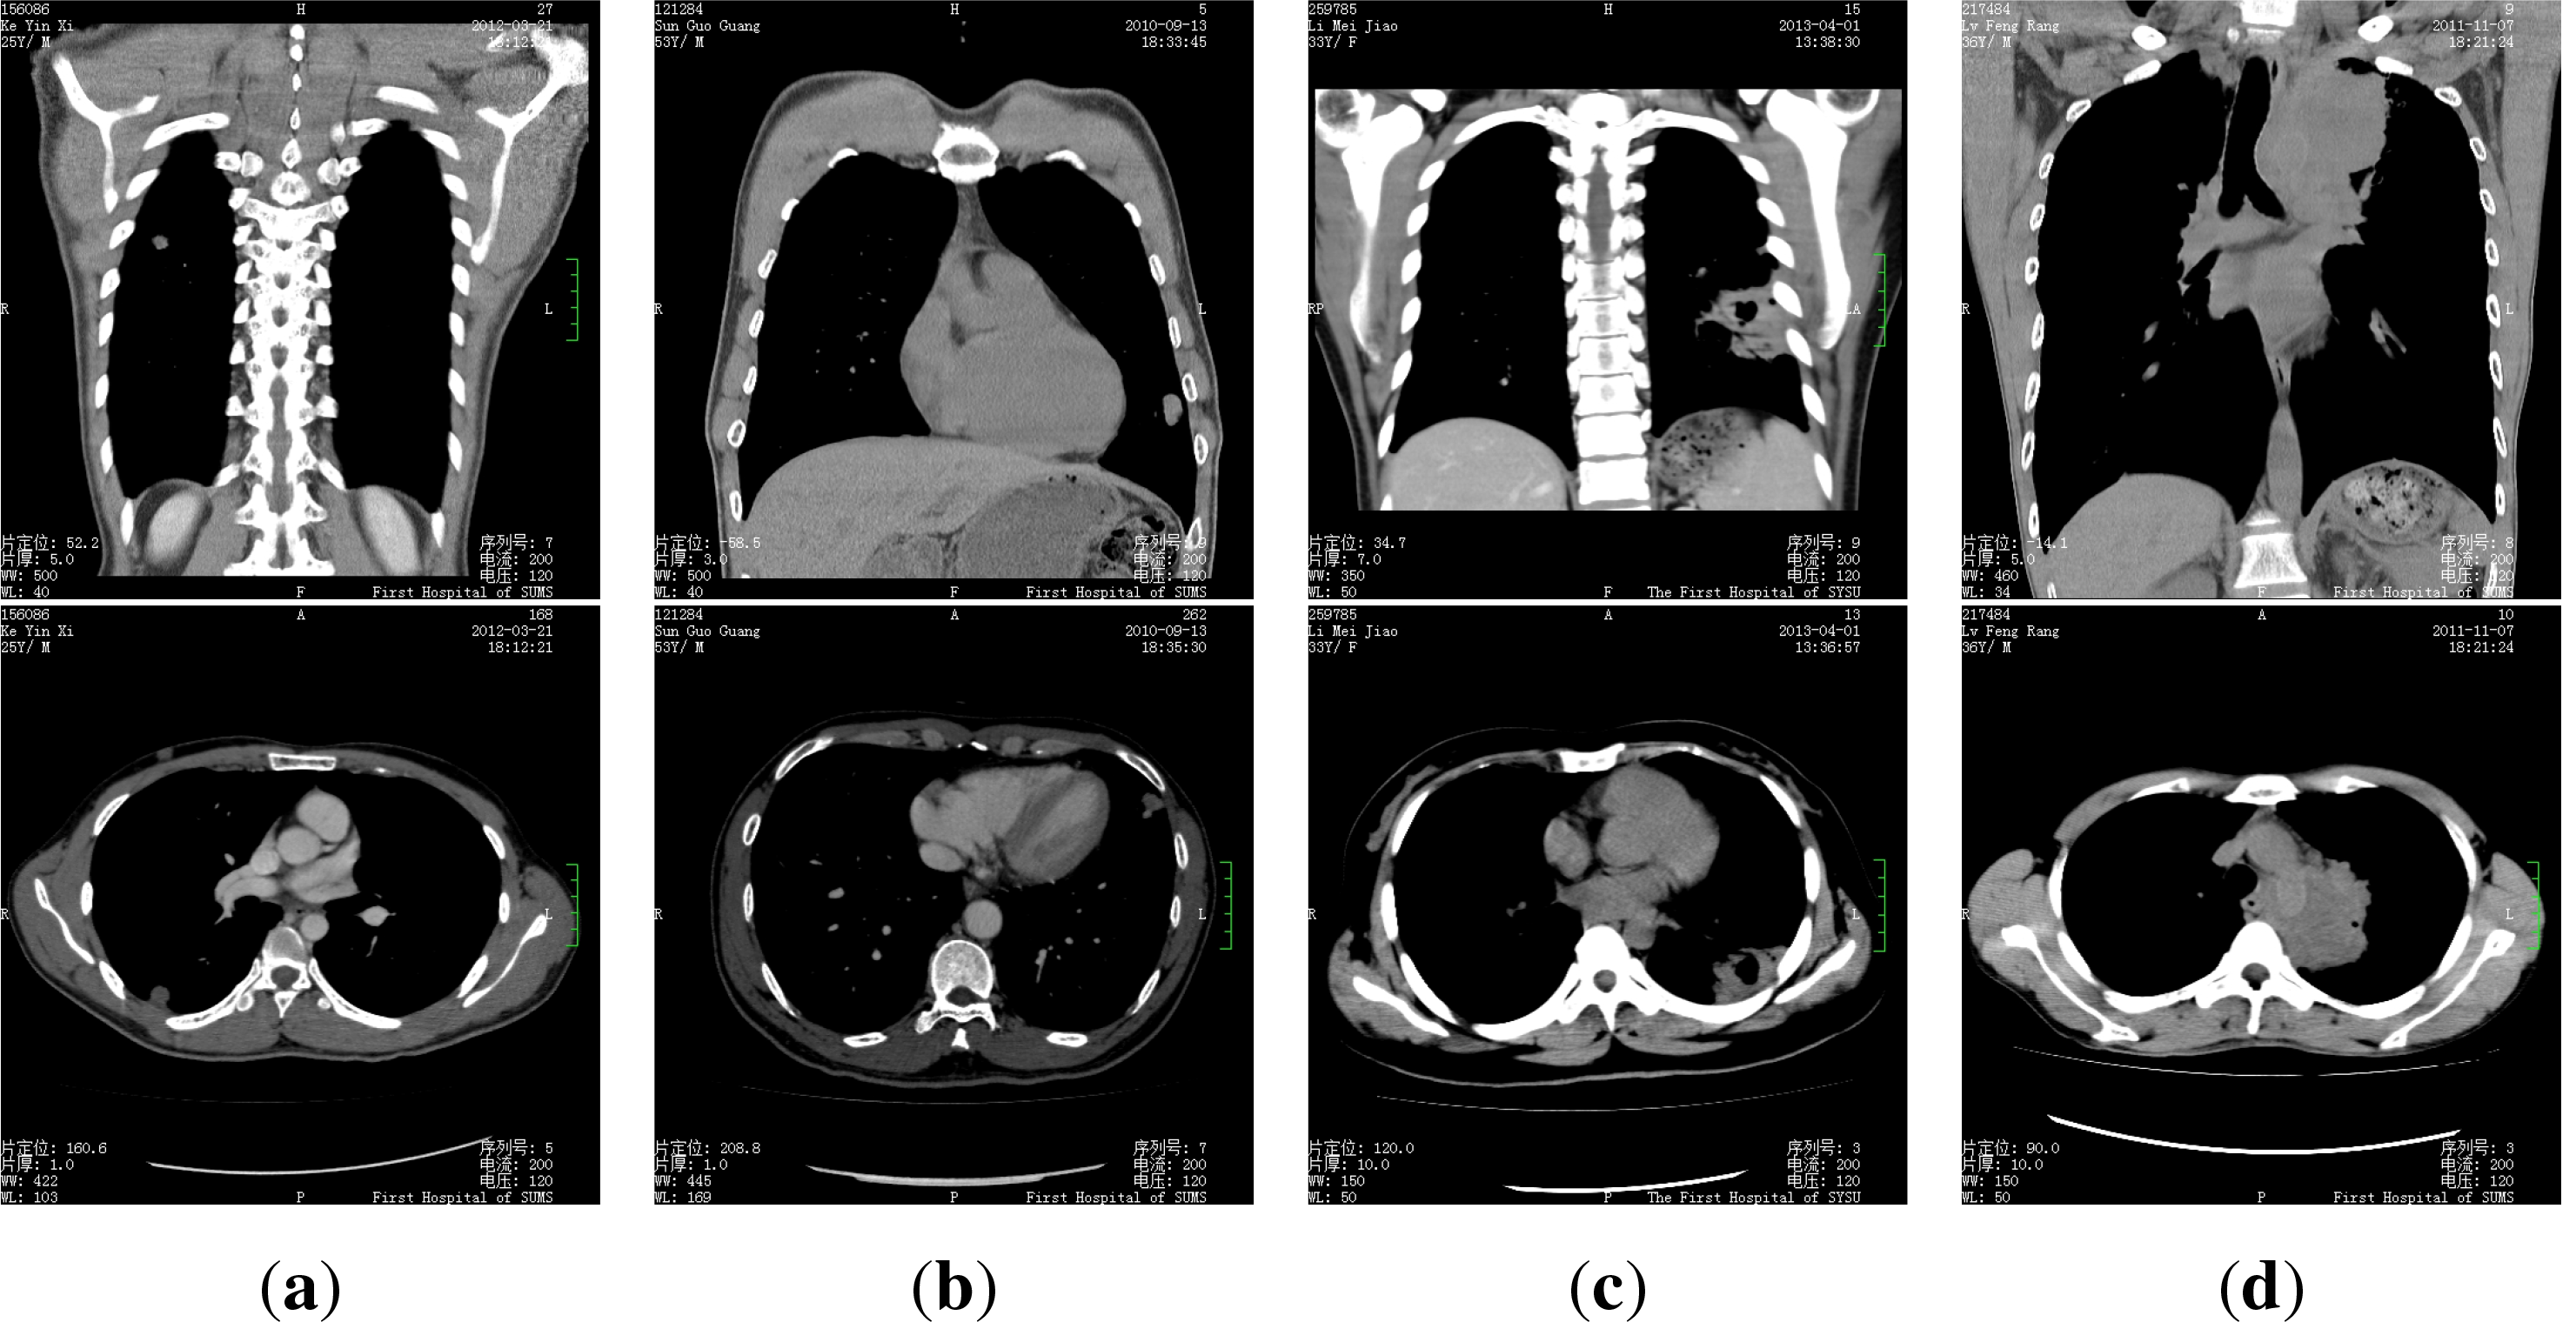

The dataset we use is composed of 50 patients’ CT medical images, for every patient there are 300–400 images. Every patient is in one of the four categories: pulmonary tuberculosis, lung cancer, pulmonary abscess and pulmonary metastasis, some samples of the images are presented in Figure 2.

Figure 2.

Some sample medical images, (a) pulmonary tuberculosis; (b) lung cancer; (c) pulmonary abscess; (d) pulmonary metastasis.

We recruit 13 volunteers to diagnose (or to label) the patients according to their images, all the volunteers are 2nd or 3rd year graduate students of the medical imaging major. We ask every student to make their diagnosis for every patient according to the images independently. The average accuracy of the volunteers is 39.54%, i.e., on average, every student only has 19 accurate diagnosis. Besides, the best volunteer achieved an accuracy of 50%, while the worst one only has a accuracy of 20%.